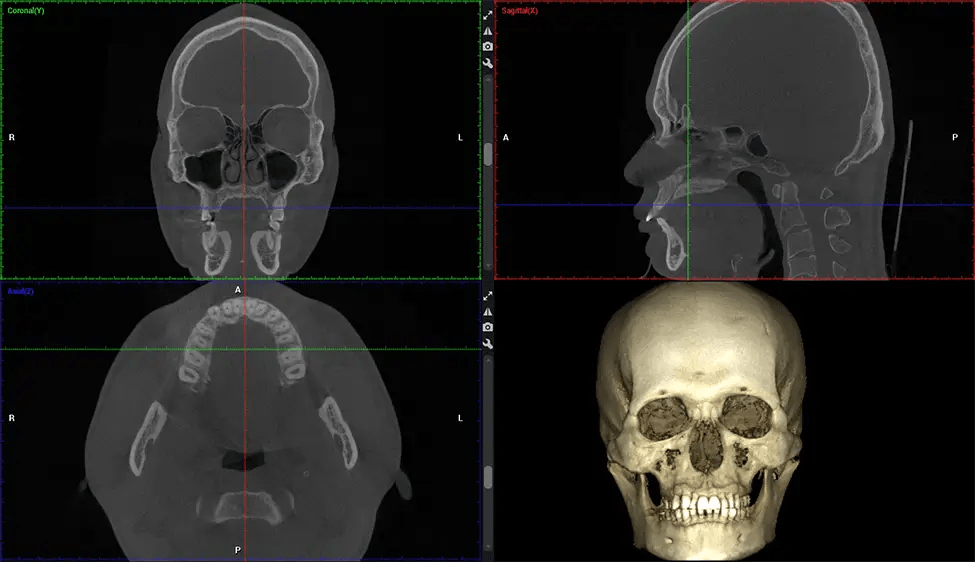

The patient is first positioned in the CBCT scanner, which typically consists of a rotating arm that houses the X-ray source and a detector. The patient’s head is immobilized to ensure accurate image capture. The X-ray source and detector rotate around the patient’s head, capturing various X-ray images from multiple angles. As the X-ray source rotates, it emits the cone-shaped X-ray beam towards the detector. The detector captures the X-ray images, which are then processed by the CBCT software.

After the scanning process, the captured X-ray images are processed by the CBCT software, which applies algorithms to reconstruct a detailed 3D image of the scanned area. The software compiles these individual X-ray images and creates a digital 3D representation of the patient’s anatomy. The reconstructed 3D CBCT image can be viewed and analyzed by the dentist or radiologist. This image can be manipulated, rotated, and zoomed in or out to examine specific structures and evaluate the patient’s condition.